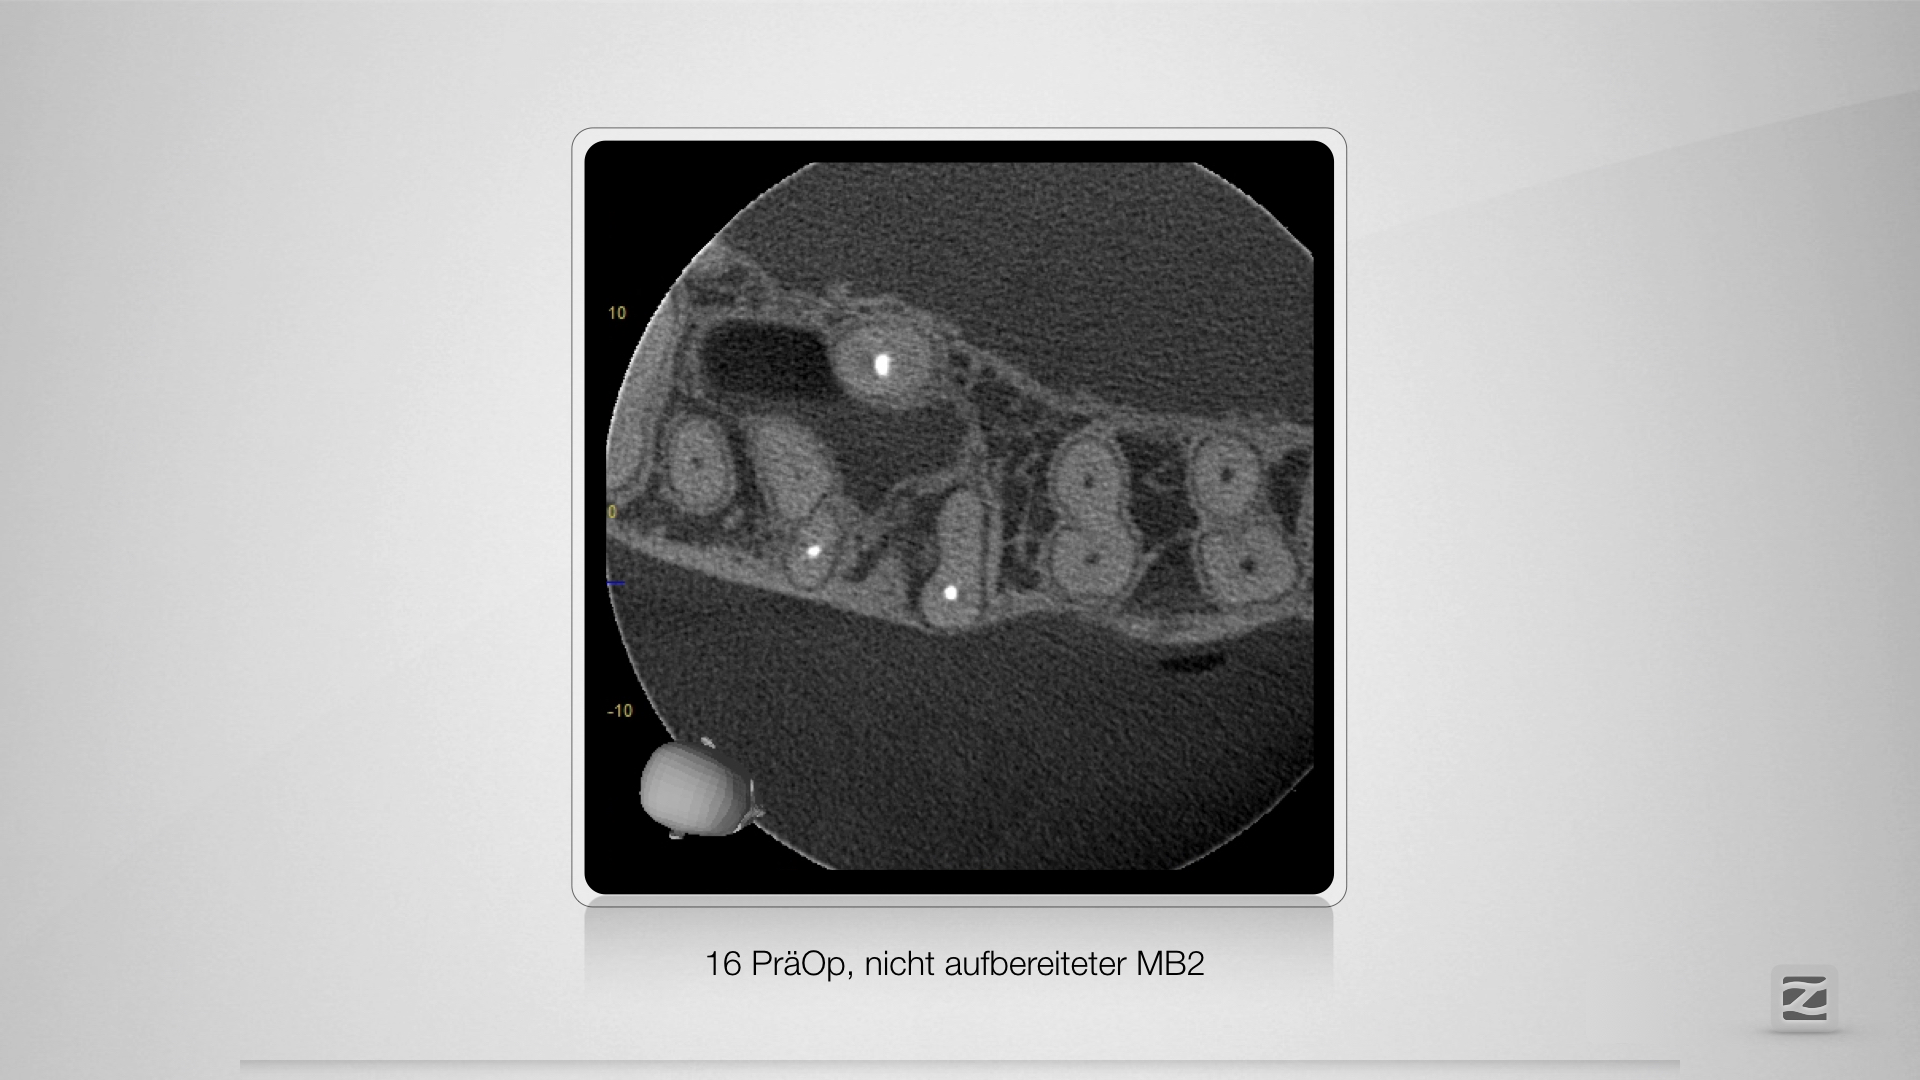

16D.003

Selektive Revision